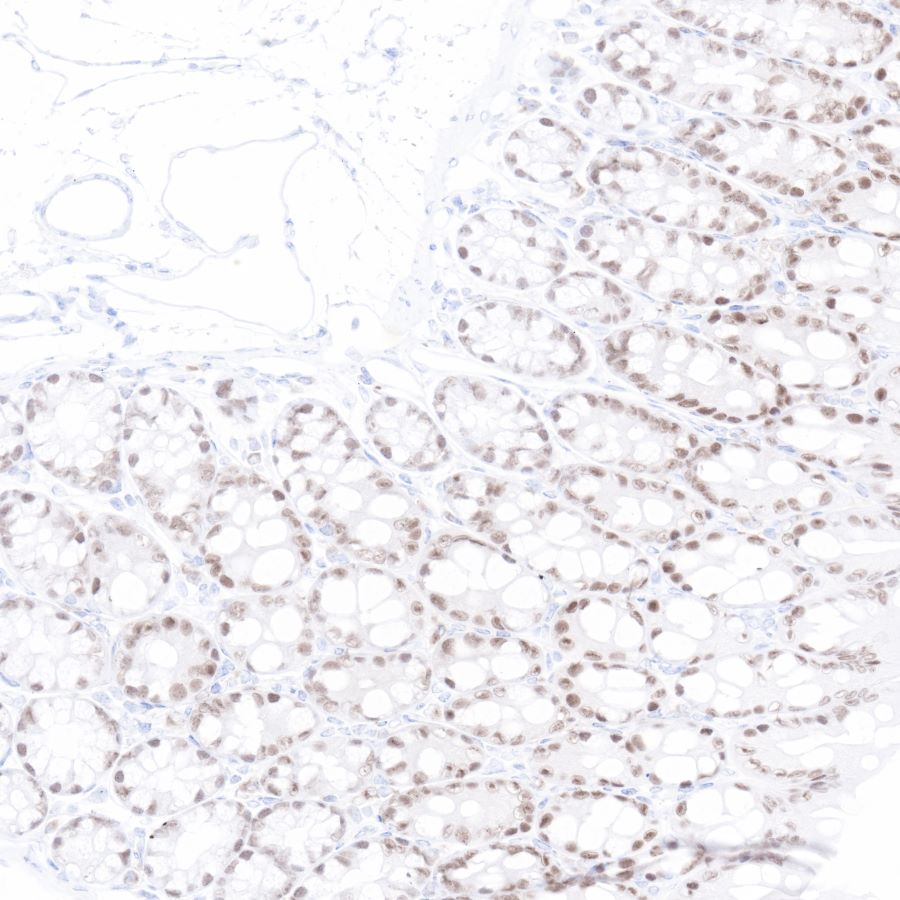

IHC shows positive staining in paraffin-embedded human colon. Anti-CDX2 antibody was used at 1/500 dilution, Secondary antibody: #JP20040. Counterstained with hematoxylin. Heat mediated antigen retrieval with Tris/EDTA buffer pH9.0 was performed before commencing with IHC staining protocol.

IHC shows positive staining in paraffin-embedded human colon cancer. Anti-CDX2 antibody was used at 1/500 dilution, Secondary antibody: #JP20040. Counterstained with hematoxylin. Heat mediated antigen retrieval with Tris/EDTA buffer pH9.0 was performed before commencing with IHC staining protocol.

IHC shows negative staining in paraffin-embedded human kidney. Anti-CDX2 antibody was used at 1/500 dilution, Secondary antibody: #JP20040. Counterstained with hematoxylin. Heat mediated antigen retrieval with Tris/EDTA buffer pH9.0 was performed before commencing with IHC staining protocol.

IHC shows negative staining in paraffin-embedded human breast cancer. Anti-CDX2 antibody was used at 1/500 dilution, Secondary antibody: #JP20040. Counterstained with hematoxylin. Heat mediated antigen retrieval with Tris/EDTA buffer pH9.0 was performed before commencing with IHC staining protocol.

IHC shows positive staining in paraffin-embedded mouse colon. Anti-CDX2 antibody was used at 1/500 dilution, Secondary antibody: #JP20040. Counterstained with hematoxylin. Heat mediated antigen retrieval with Tris/EDTA buffer pH9.0 was performed before commencing with IHC staining protocol.

IHC shows positive staining in paraffin-embedded rat colon. Anti-CDX2 antibody was used at 1/500 dilution, Secondary antibody: #JP20040. Counterstained with hematoxylin. Heat mediated antigen retrieval with Tris/EDTA buffer pH9.0 was performed before commencing with IHC staining protocol.